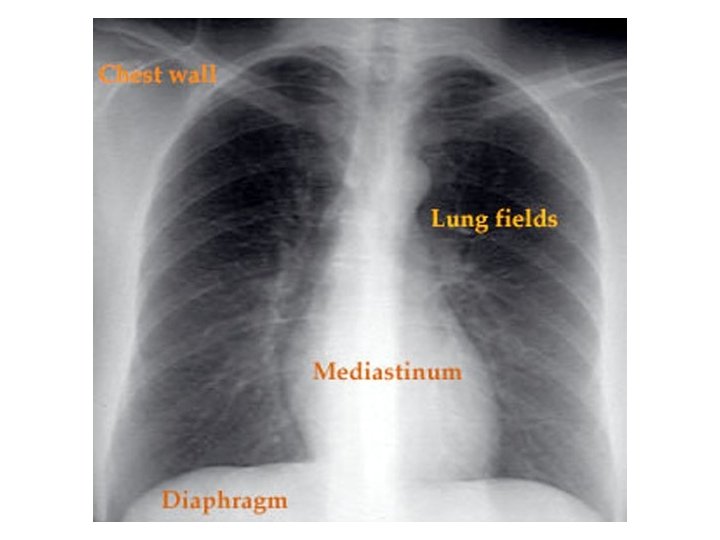

Chest X-ray Path correlation • • • Normal structures Densities Genesis of abnormal densities

Chest X-ray Path correlation • • • Normal structures Densities Genesis of abnormal densities Localization Pathological correlation Steps in evaluation of CXR

Localization • • Lobar distribution Air bronchogram Silouhette sign Extra pleural sign